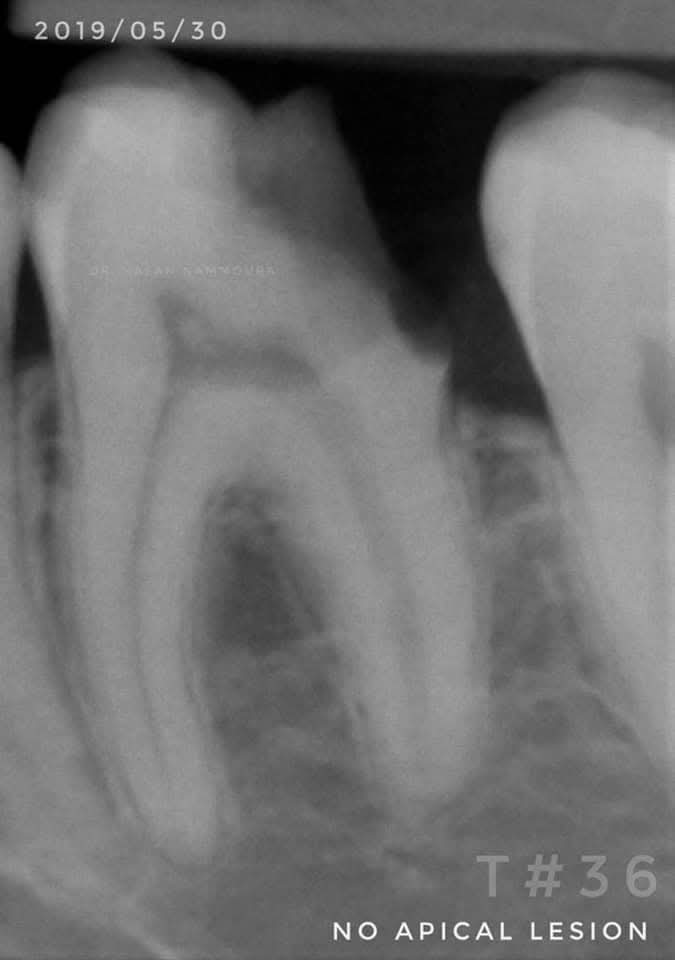

A 25-year-old patient presented with cold and sweet sensitivity. Tooth #36 showed a deep lesion but no periapical pathology. After rubber dam isolation, selective caries removal was performed. MTA was used for pulp capping, followed by a resin-modified glass ionomer liner (VitreBond, 3M), flowable bulk-fill composite, and immediate dentin sealing. The tooth was prepared for a CAD/CAM overlay, milled with CEREC, and bonded under isolation.

Post-treatment, the tooth remained vital and asymptomatic. Follow-up at 1, 3, and 6 years confirmed continued vitality, normal periapical structures, and no restoration failure. The 6-year radiograph showed no signs of pathology, with stable margins and no resorption.